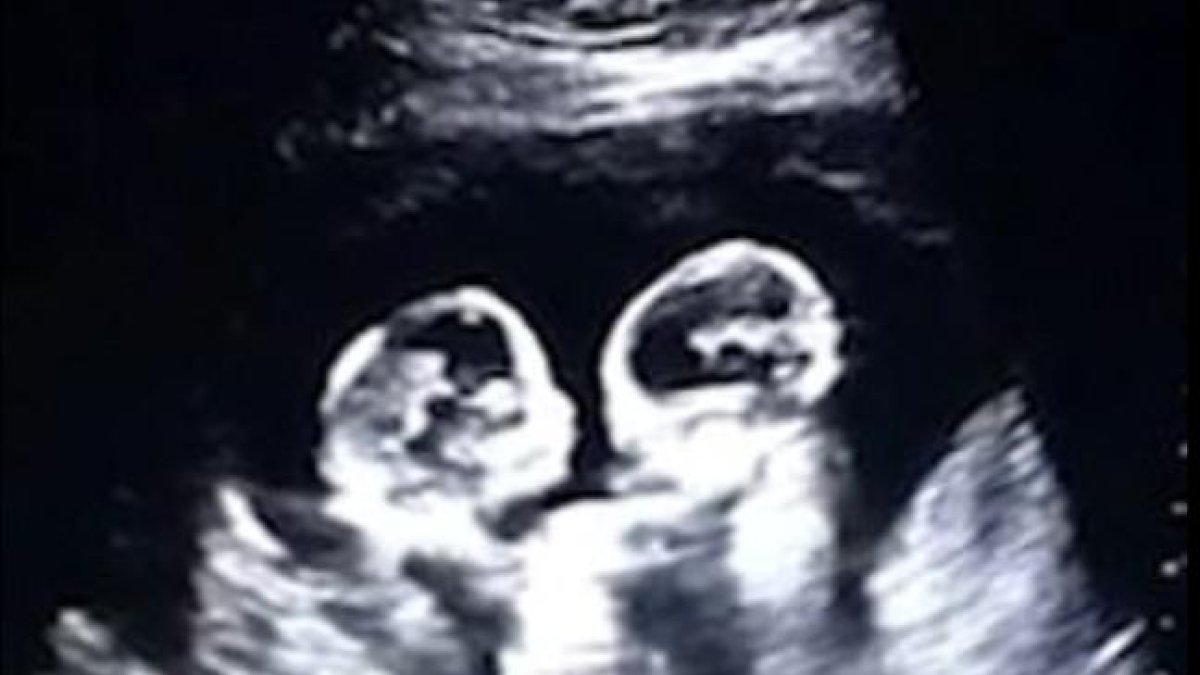

El audiovisual muestra el momento en que una de las gemelas golpea a su hermana con el brazo.

Una ecografía donde se ve a una gemelas aparentemente golpeándose dentro del vientre de su madre, sorprendió en el hospital Yinchuan, en China.

El video, compartido por el portal China Daily, muestra a las bebés cara a cara cuando una de ellas lanza su mano sobre el rostro de su hermana. Ambas compartian saco anmiótico y placenta.